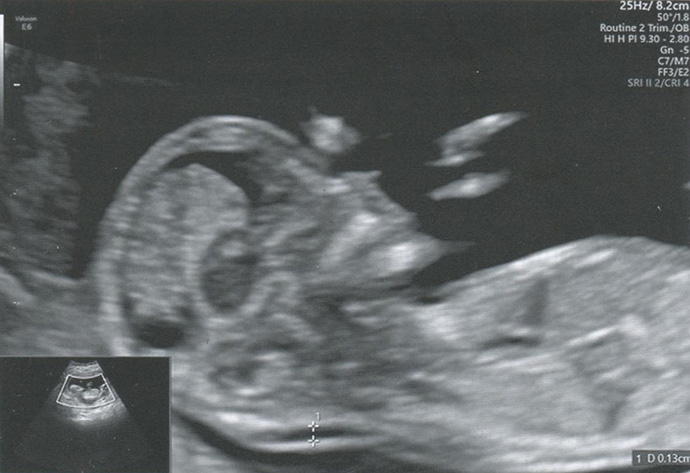

Ультразвуковое исследование

Контрон СИГМА 210, ирис. Электронные линейный датчик 7,5 МГц и конвексный - 3,5 МГц

Протокол ультразвукового исследования печени

(УЗИ шаблон (пример, бланк) протокола ультразвукового описания патологии печени)

Печень - границы печени не расширены: нижний край правой доли у рёберной дуги, незначительно закруглён, переднезадний размер правой доли 119 мм, косой вертикальный 148 мм, переднезадний размер левой доли 59 мм, вертикальный 93 мм; контуры ровные, диафрагмальный контур нечёткий, паренхима неоднородная за счет гипоэхогенного участка вблизи правой боковой стенки желчного пузыря, имеющего округлую форму, диаметром 15 мм, имеющего ровные, относительно четкие контуры, однородное внутреннее строение; на остальном протяжении паренхима однородная, эхоструктура диффузно повышенной эхогенности рисунок зернистости нечёткий; внутрипечёночные жёлчные протоки не расширены, свободны, сосудистый рисунок обеднен.

Общий жёлчный проток диаметром 4 мм, стенки не утолщены, просвет свободный.

Регионарные лимфатические узлы не визуализируются.

Заключение

Эхографические признаки хронического гепатита, гипоэхогенного очага 5 сегмента печени.

Ультразвуковая диагностика не является основным методом и требует подтверждения диагноза другими методами обследования.